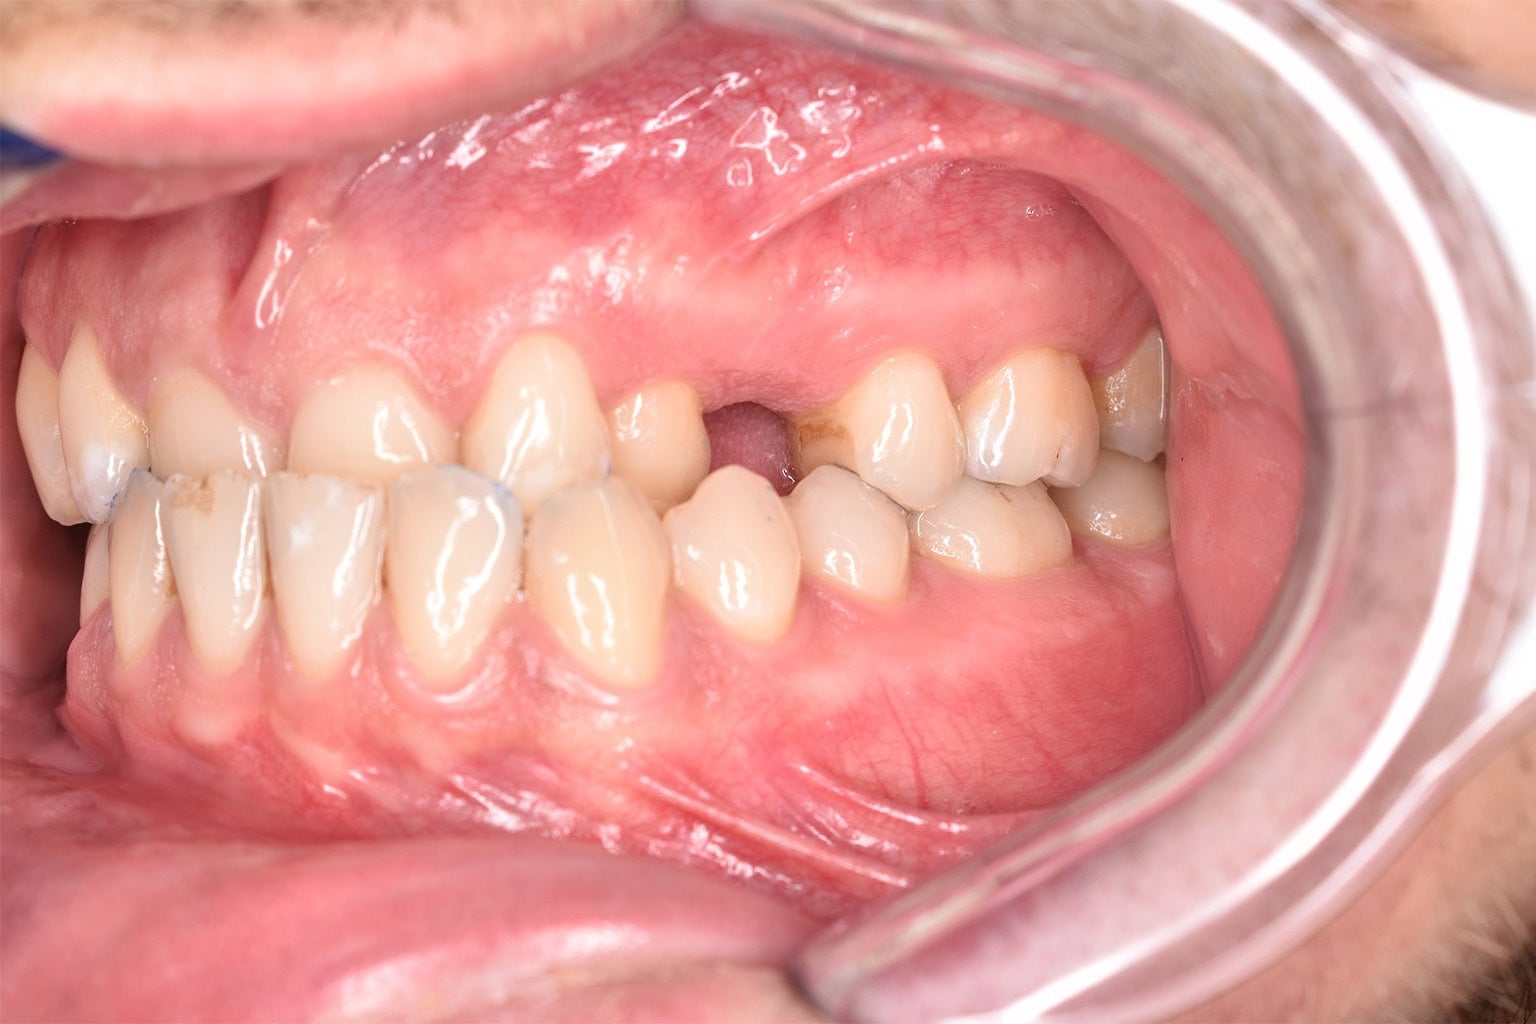

Vorher-Nachher-Ergebnisse

Echte Ergebnisse. Echte Menschen.

Jede Behandlung bei TIEFBLAU Kieferorthopädie ist so individuell wie der Mensch dahinter. In unserer Vorher-Nachher-Galerie zeigen wir Ihnen echte Behandlungsergebnisse aus unserer Praxis in der Kölner Südstadt: Schonend erzielt, präzise geplant und mit dem Anspruch, den wir seit über 40 Jahren an jede Behandlung stellen.

Die Bilder geben Ihnen einen Eindruck davon, was moderne Kieferorthopädie leisten kann, ob bei Kindern, Jugendlichen oder Erwachsenen.

Der sichtbare Unterschied

Dokumentiert. Überzeugend. Nachhaltig.